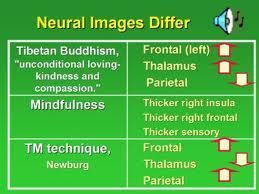

4. What parts of the brain are used in meditation and what types of meditation use what parts most?

image from http://www.8limbsholistichealth.com

For me, the thalamus and frontal areas were most impacted and affected, so far, since the front of my face/forehead hit the wall, and since those areas are involved in my type of meditation. However, I could imagine that other injuries/affected areas could impact your meditation differently.

5. What about different kinds of meditation and where in the brain they occur?

image from http://www.fredtravis.com

Definitely the thalamus and all frontal areas are affected, for me. I guess I don’t feel the impact in the pariental lobe because mine wasn’t so injured. Again, your experiences could vary a lot.